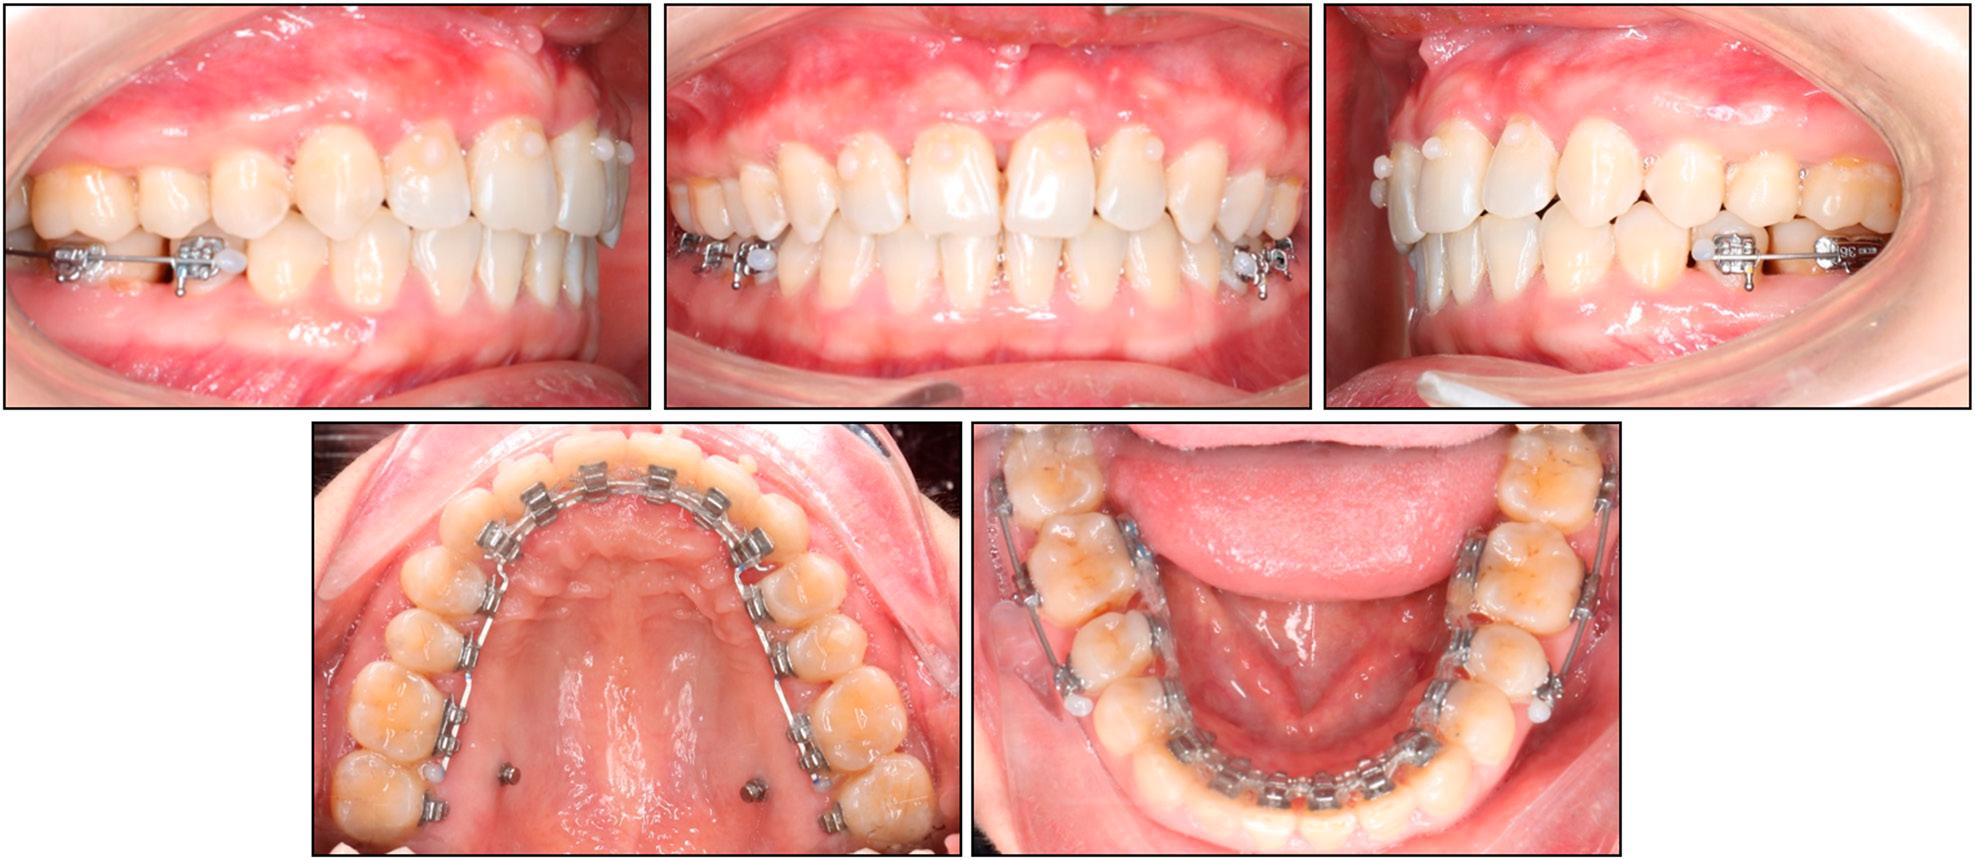

Figure 3.